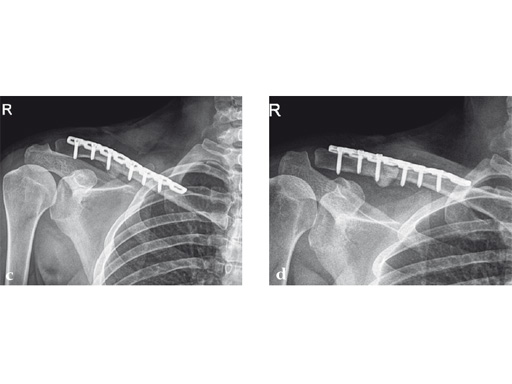

Case 1: a 30-year-old woman sustained a midshaft clavicle fracture. it healed with 2.1 cm shortening over 4 years after nonoperative treatment.

Case provided by Norbert Sdkamp and Martin Jaeger, Freiburg, Germany